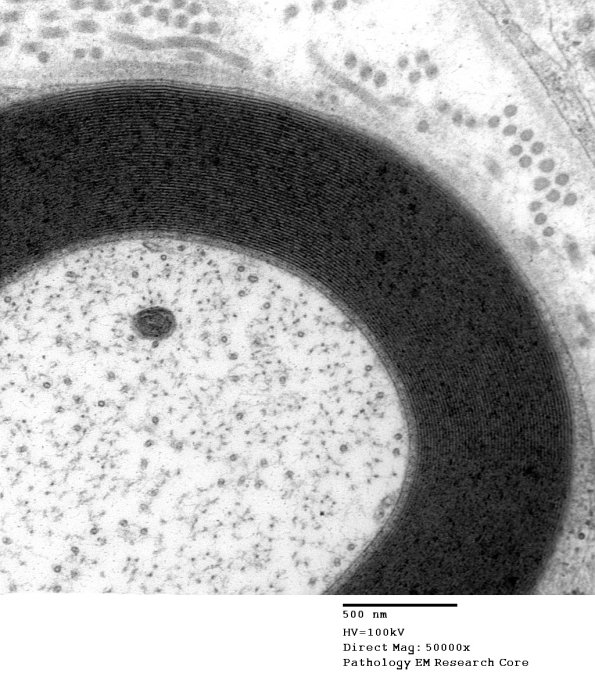

A normal myelinated axon and its cytoskeletal elements. (electron micrographs)